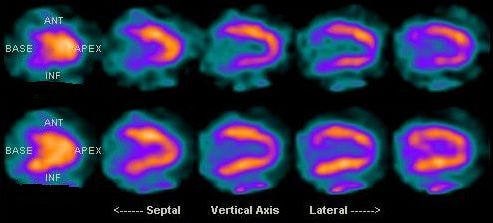

Scintigrafia miocardica

By KieranMaher at English Wikibooks – Transferred from en.wikibooks to Commons by Dirk Hünniger., Public Domain, Link

Permette lo studio del flusso delle coronarie permettendo la discriminazione tra:

- aree perfuse normalmente,

- aree con perfusione ridotta o del tutto assente, come in caso di infarto.

Il tracciate radioattivo nella maggior parte dei casi è il sestamibi marcato con Tecnezio-99 metastabile (99mTc).

Grazie alla scintigrafia cardiaca è possibile:

- confermare o escludere un’insufficienza cardiaca quando altri esami hanno fornito risultati dubbi,

- valutare l’estensione dell’infarto,

- valutare l’efficacia di una procedura di rivascolarizzazione qualora persistano i sintomi,

- confermare o escludere di un infarto in assenza alterazioni all’ECG o di aumenti della troponina.